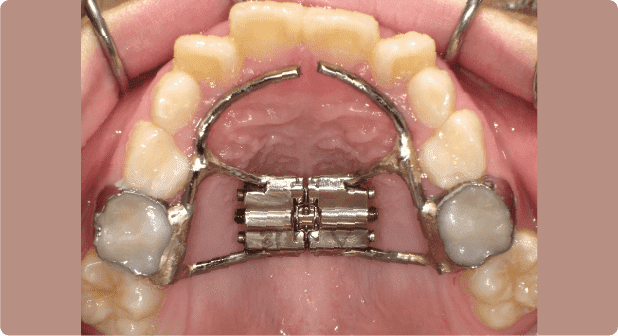

Q 装置は治療期間中ずっとつける必要があるのですか?

治療の開始から終わりまで、ずっと装置が入っていることはありません。

装置は、短いもので半年くらい、長いもので1~2年使用します。あごの発育や乳歯から永久歯への生えかわりの際に必要に応じて使用装置を作りかえ、治療を進めていきます。

固定式の装置を装着した直後は、食事や会話に不自由を感じることもありますが、数日で慣れます。